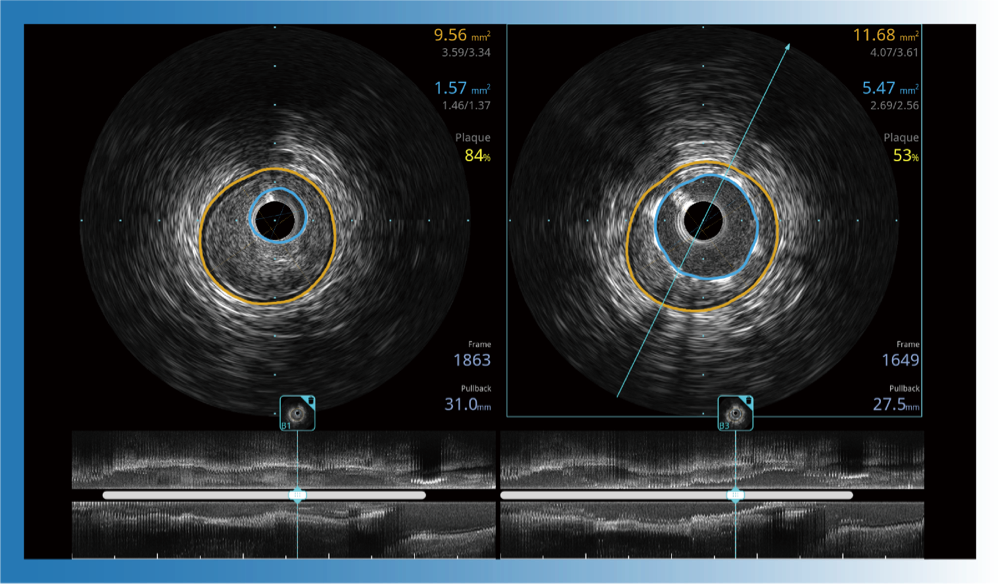

治療前后兩次測量錄像對比

簡化療效評估

一鍵智能描跡,自動測量斑塊負(fù)荷、面積狹窄率等指標(biāo),準(zhǔn)確率高于90%